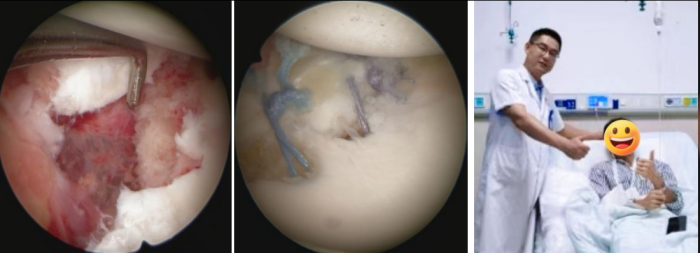

考虑到患者年轻且有强烈的运动需求,运动医学科团队为他实施了关节镜下微创修复手术。通过三个几毫米的小切口,精准地将撕脱的骨折块和盂唇组织复位到原位,并将它们牢固地重新固定在了肩胛盂上,恢复了肩关节稳定性结构,患者术后恢复良好,现已进入个性化的康复阶段。

关节镜下微创修复手术,患者术后恢复良好